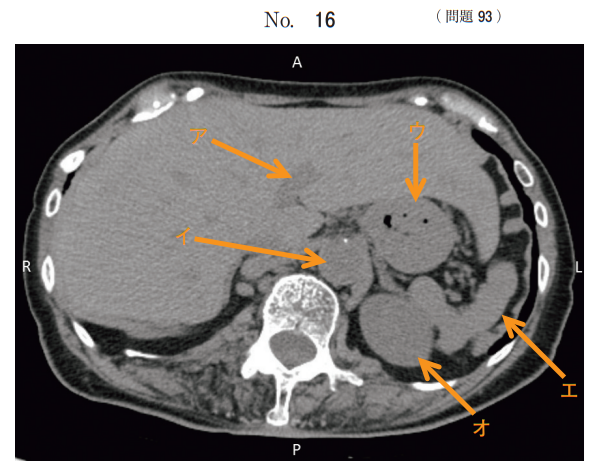

午後/問題93

腹部 CT 像(別冊No. 16)を別に示す。

正しい組合せはどれか。

1.ア 門 脈

2.イ 下大静脈

3.ウ 横行結腸

4.エ 膵 臓

5.オ 副 腎

答え

1